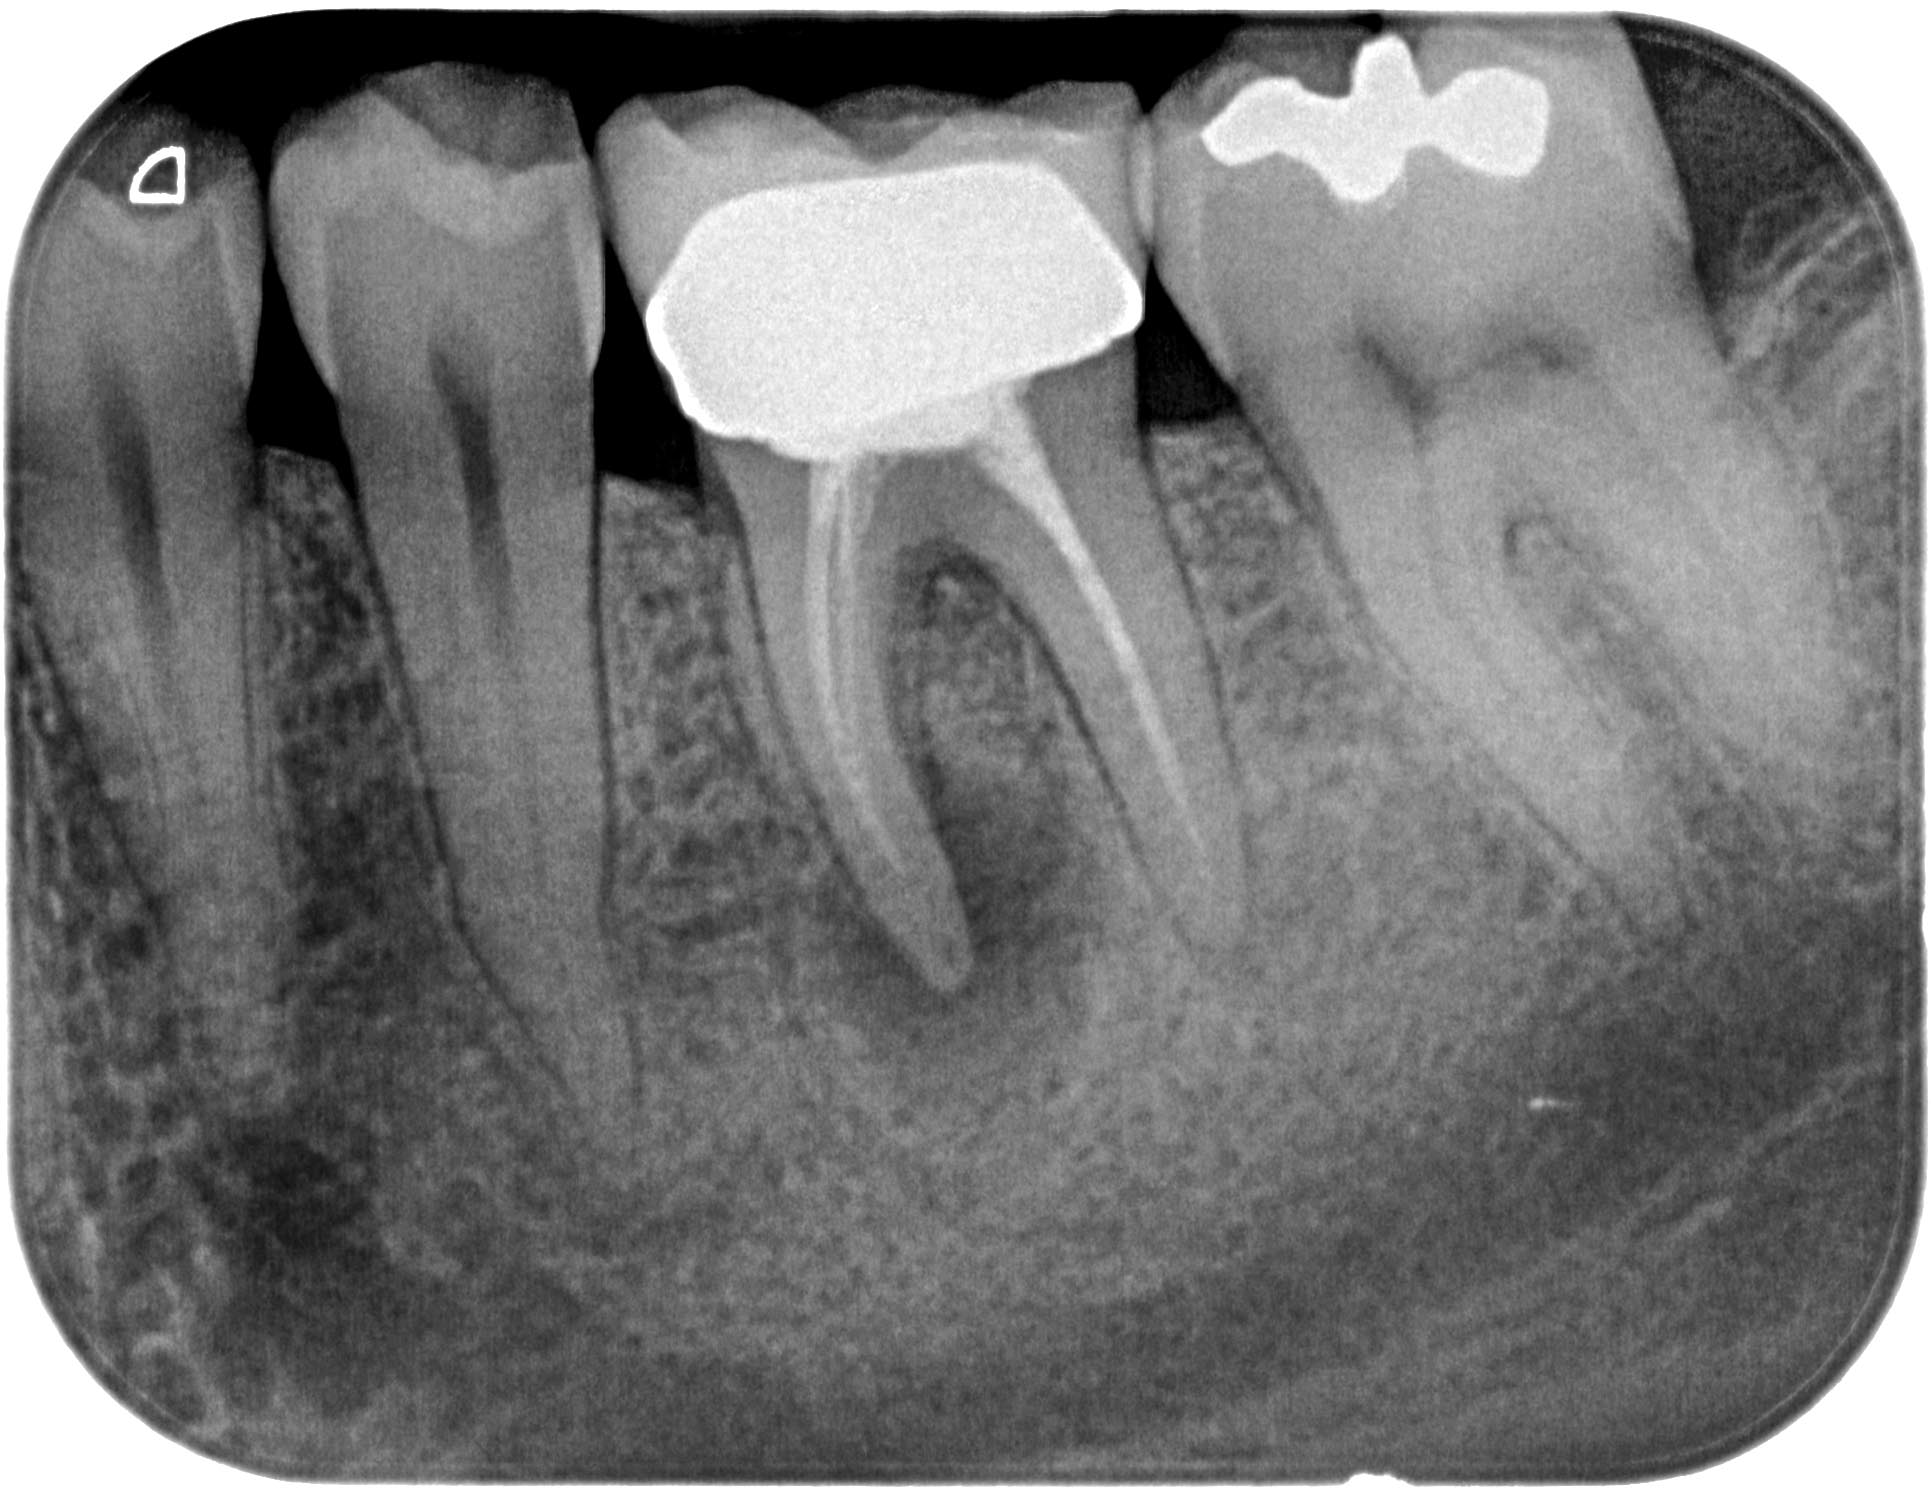

FM36 (2 von 6) Veröffentlicht 21. März 2016 am 1931 × 1489 in Calciumhydroxid- Überpressung (2) 13. Januar 2012